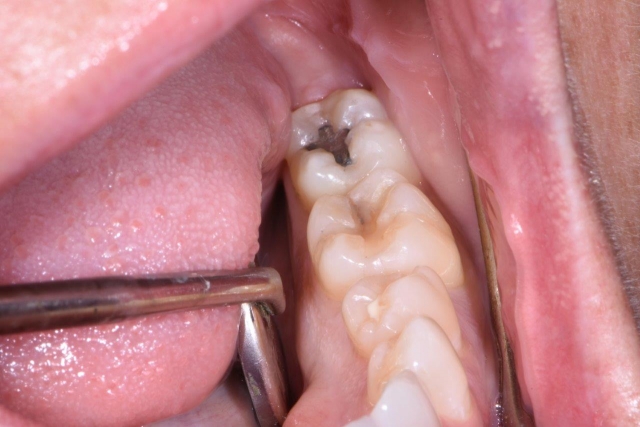

The last two types of cracked teeth, fractured cusp and cracked tooth, get a lot more interesting. We as clinicians have to manage each patient and tooth individually, because every situation can have a different set of variables. It can vary from a completely asymptomatic fracture noted upon removal of an old restoration to a tooth that has constant pain upon biting and thermal sensitivity to one that has a fractured cusp present with no sensitivity. Do you treat each of these the same? No. If not, how do you manage them? Here are some insight and guidelines on how to manage that cracked tooth or fractured cusp:

Once you’ve gathered data and developed a working diagnosis on the tooth in question, you have to determine the extent of the crack and whether the pulp is involved and healthy. If the pulp is healthy and stable, then is it a fractured cusp we are managing, or a cracked tooth? If it’s a fractured cusp, we have to look at removing the fractured cusp and assess the remaining tooth structure. If enough tooth remains, it may be possible to do a direct restoration to manage the situation. If not, then the tooth may require an inlay, an onlay or a build-up and crown.

If it’s a cracked tooth rather than a fractured cusp, the fracture/crack tends to be more centered in the tooth and, if not managed or treated properly, will lead to a split tooth and eventual tooth loss. In these situations, it’s recommended that the patient be informed of the guarded long-term prognosis of the pulp and/or tooth before pursuing treatment. Even with our best efforts, a cracked tooth can eventually get worse and lead to pulpal necrosis or a split tooth and tooth loss.

With a cracked tooth in which the pulp is involved and irreversibly inflamed and/or necrotic, the tooth will need root canal treatment along with assessing how deep the crack goes. Is it just into the pulp chamber or is it deep into the pulpal floor and down into the root itself? The deeper the crack, the more concerned we have to be about the long-term prognosis and whether the tooth will become a split tooth and eventually be lost.

If the pulp is healthy and intact, then the goal is keep the crack from getting worse. Covering the crack in its entirety will also keep bacteria from invading deeper into the tooth and leading to pulpal necrosis or future tooth loss. We also want to alleviate any symptoms prior to completing the final restoration.